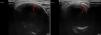

Se completa estudio mediante una tomografía computarizada (TC), donde se confirma una lesión quística expansiva, sin afectación de partes blandas, que sugiere probable quiste odontogénico calcificante (QOC) (fig. 3).

Tomografía computarizada, ventana hueso. A) Reconstrucción curva: lesión quística expansiva y multiloculada, localizada en cuerpo y rama mandibulares izquierdos, con fino tabique interno y leve festoneado de la cortical interna. B) Corte axial: contenido hipodenso sin afectación de partes blandas; desplazamiento de piezas dentarias.